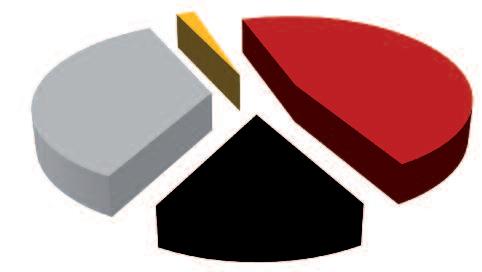

Demistificazione del cancro tramite le statistiche dell’OGM (Organizzazione Mondiale della Sanità)

Altre malattie

Malattie cardiocircolatorie

A. Ogni anno muoiono di cancro 7,5 milioni di persone

Altre malattie Infezioni Infezioni

Malattie cardiocircolatorie

B. Solo in Nord America e in Europa ogni anno muoiono di cancro 5,6 milioni di persone